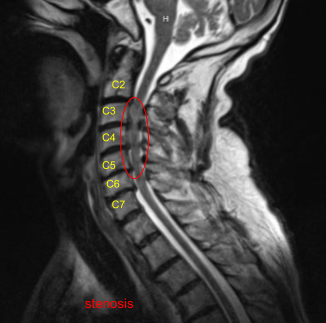

An MRI was done and found to have severe stenosis on C3-4 with moderate to severe stenosis on C4-5 and C5-6. Dr. Mariwalla and I discussed treatment options and the patient opted for surgical management. We discussed the need for anterior cervical discectomy and placement of cages as well as screws.